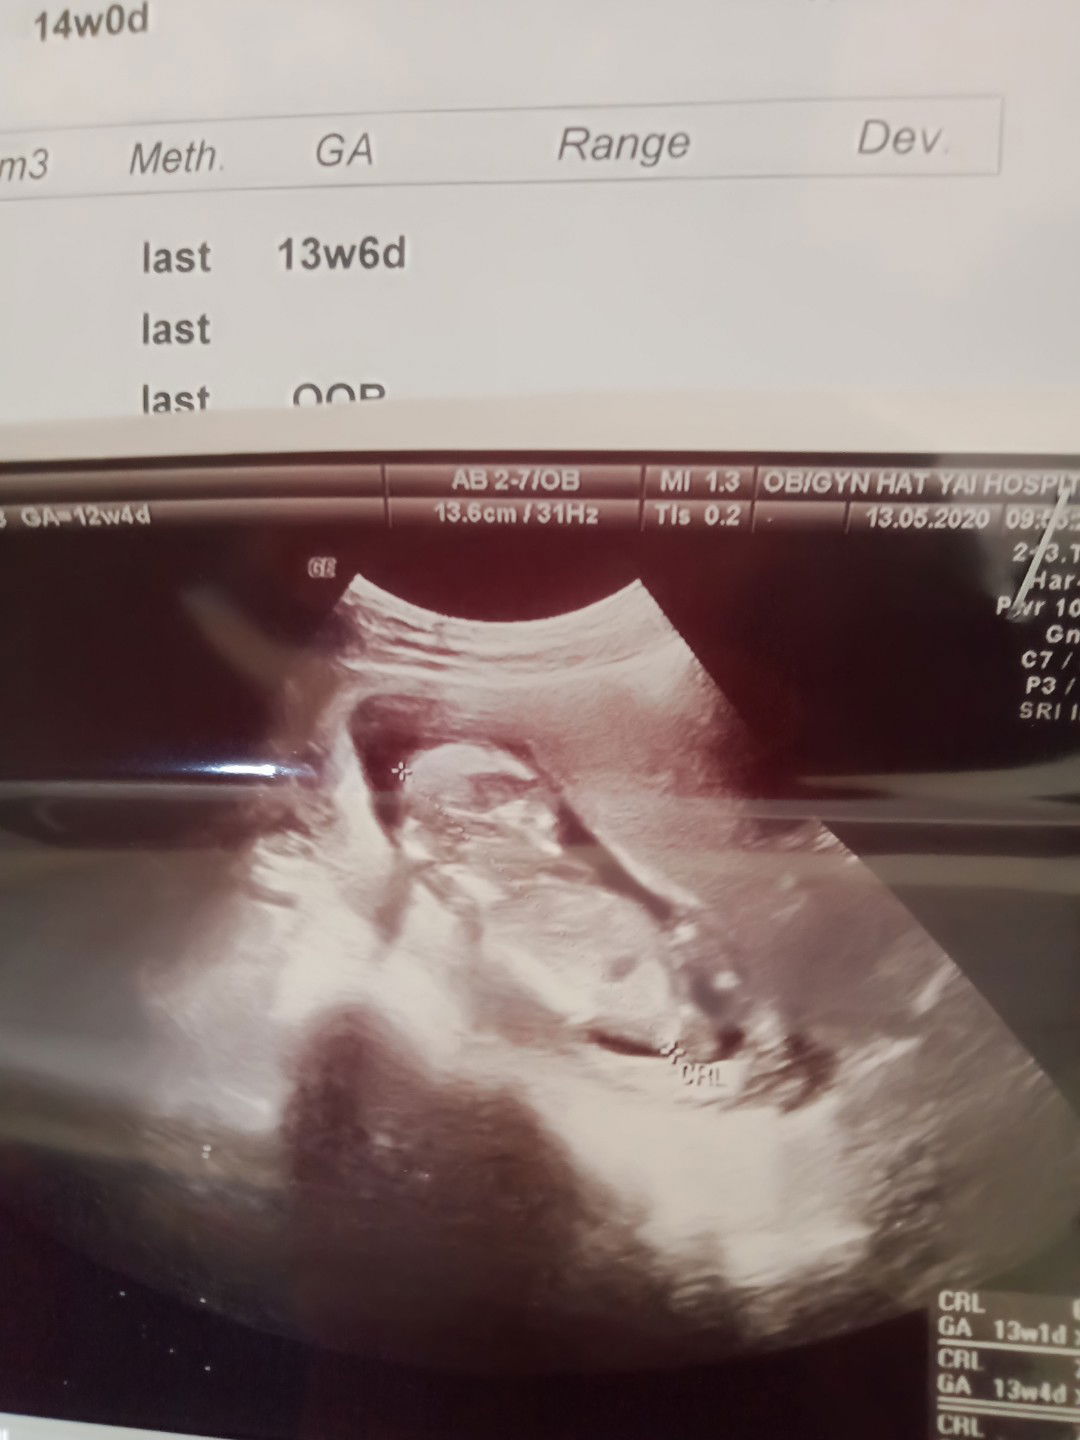

ท้อง 13 สัปดาห์ 6วัน น้ำหนักลูก 92g ไม่ทราบว่ามันตามเกณฑ์หรือเปล่า แม่ๆที่รู้ช่วยบอกหน่อยนะคะ# ท้องแรกค่ะ

น้ำหนักตามรูปเลยค่ะคุณ​แม่​